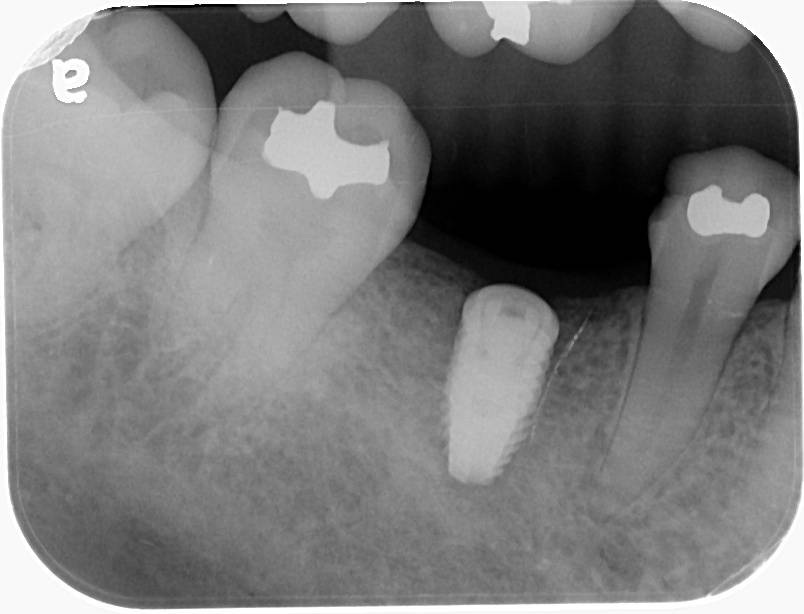

植牙後沒多久,植體出現脫落,

周圍骨頭也逐漸萎縮,

X光影像上只剩下一片明顯的黑影…

等患者再次就診時,情況已經變得更加棘手——

👉 植體已經無法維持

👉 骨頭也無法支撐新的重建

最後面對的,是一個更複雜、難度更高的缺損 💔